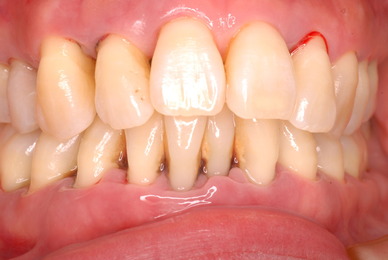

初診から数週間後大分よくなったとはいえまだまだ簡単な検査でも血だらけなのですね。